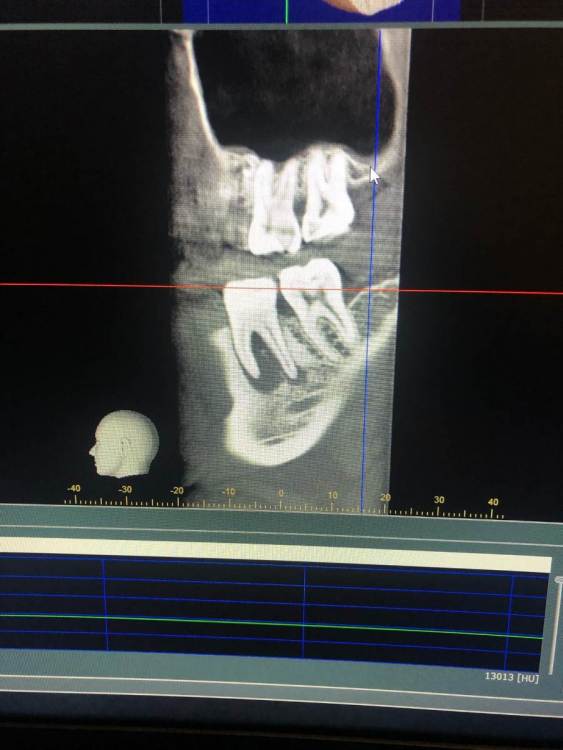

Периодонтит 4.6 с лизисом межкорневой перегородки

Немой некроз пульпы после лечения кариеса, болей не было, результат спустя 1 год и 8 месяцев, три посещения(кальций, пломбировка каналов, реставрация) кюретаж в данном случае не делал. Есть видео кт -